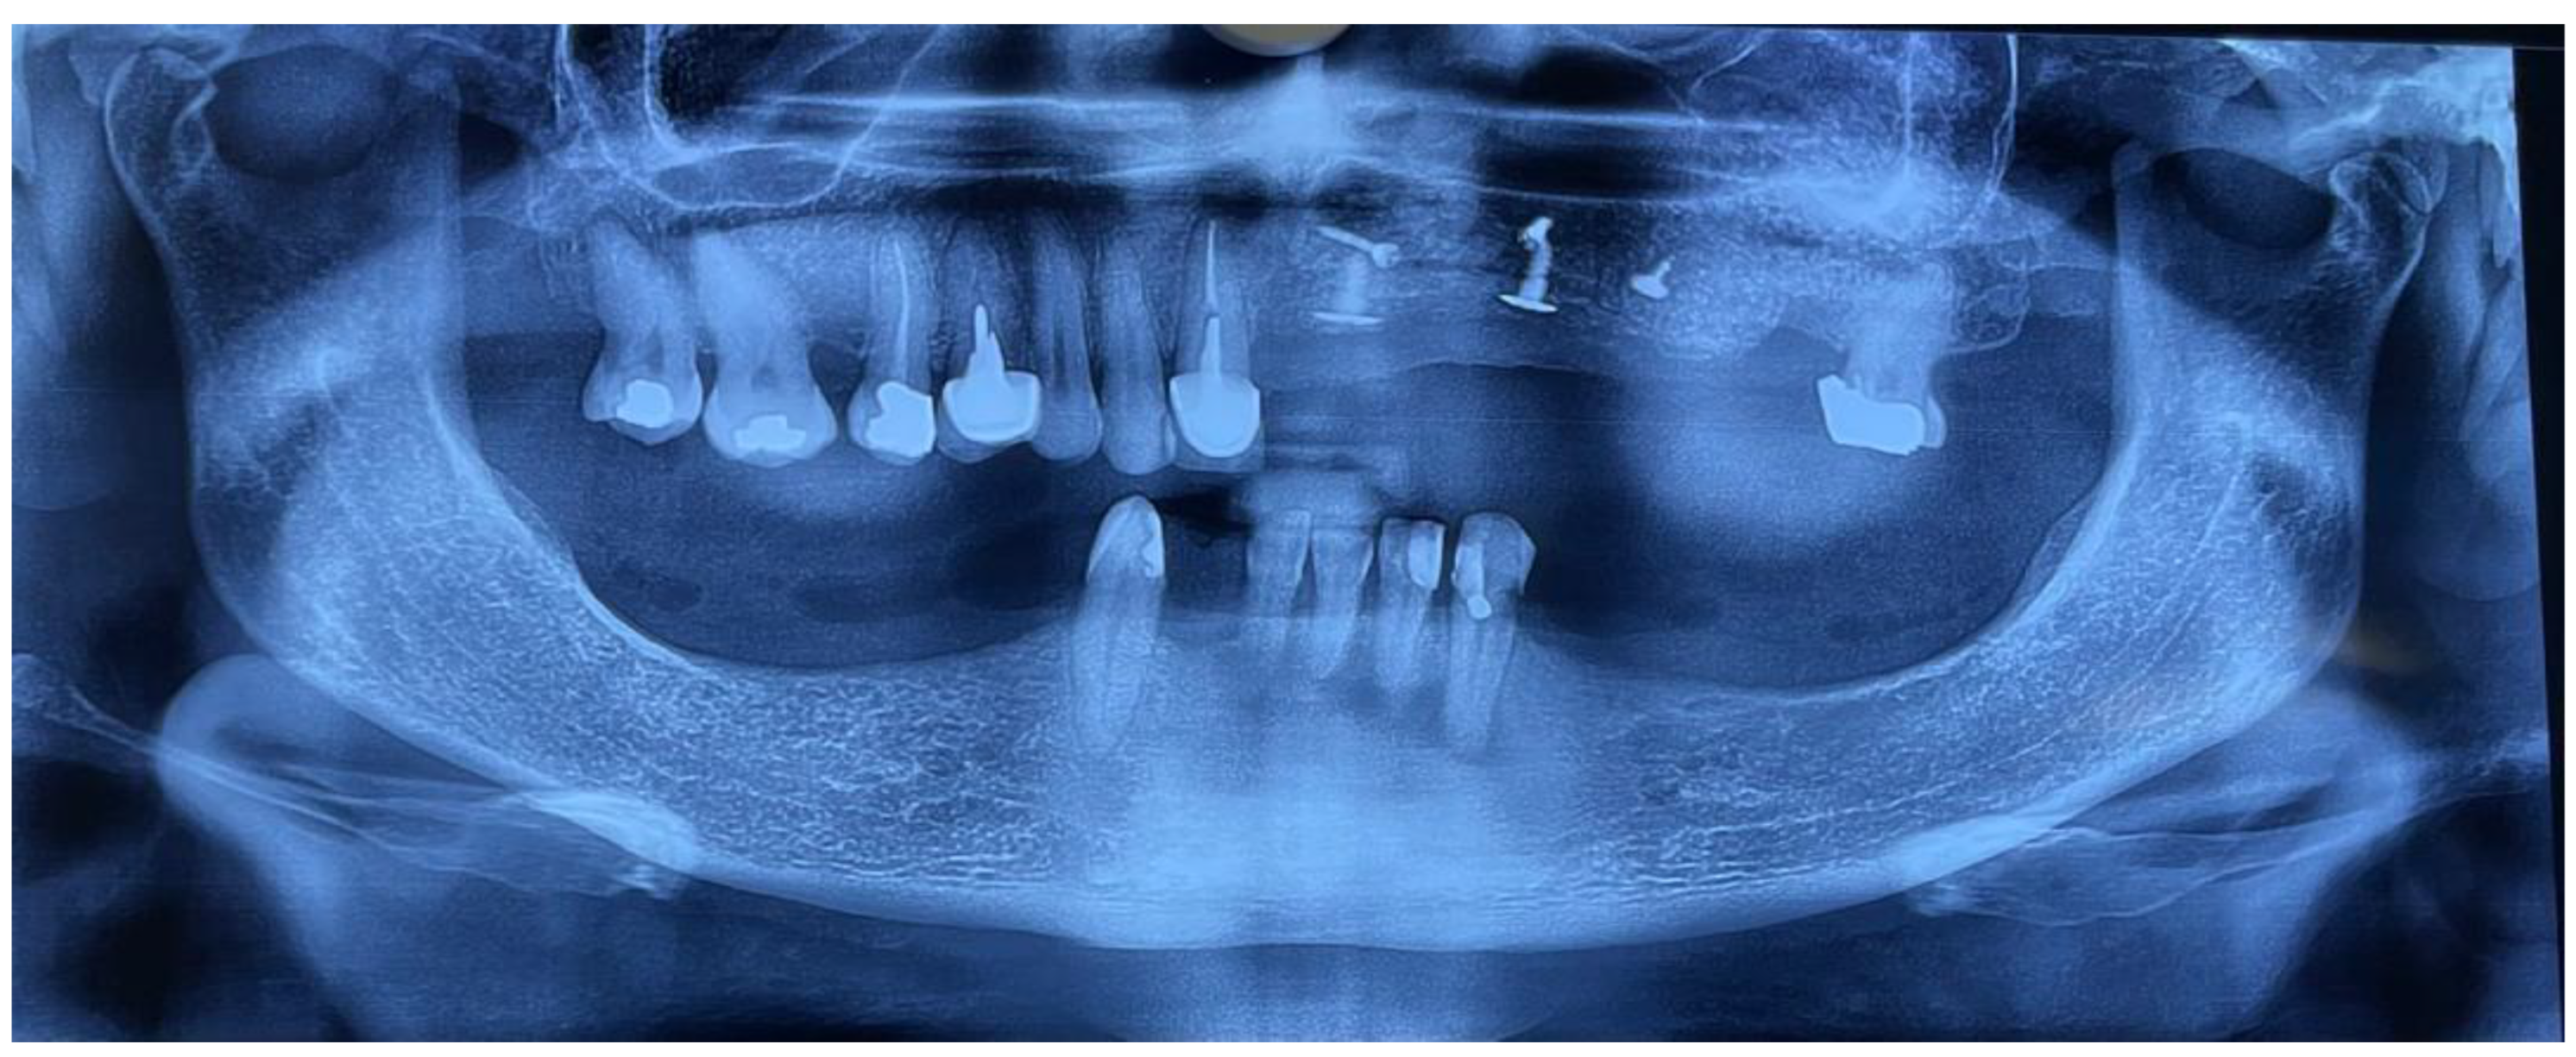

The diagnostic records, including preoperative intraoral photographs, study casts, panoramic radiographs, and CBCT scans, clearly illustrated the pronounced ridge deficiencies and the absence of keratinized mucosa in the anterior maxilla (Figure 1, Figure 2, Figure 3, Figure 4 and Figure 5).

Figure 2. Preoperative panoramic radiograph showing missing maxillary teeth and reduced alveolar height.

Figure 7. Postoperative panoramic radiograph demonstrating (A) two titanium tenting screws for vertical augmentation, (B) two bone screws fixing the allograft bone plate, (C) one tack screw stabilizing the resorbable collagen membrane, and (D) the lateral window for open sinus lift in the posterior maxilla.